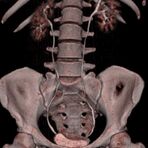

Abdomen (Bauch und Becken)

• Diagnostik von entzündlichen und tumorösen Erkrankungen der Bauchorgane

• Diagnostik von akuten Notfällen wie Darmverschluss, Hohlorganperforation oder Traumafolgen

• Darstellung der großen Gefäße zur Erkennung von Gefäßverschlüssen (z. B. Mesenterial - Arterienembolie oder Einengungen von Gefäßen (z. B. Nierenarterien)

• Darstellung und Therapieplanung von Aneurysmen (CT- Angiographie)

• Virtuelle Kolonographie zur Darstellung des Dickdarmes z. B. bei Kontraindikation zur Darm-Spiegelung oder nur unvollständig durchführbarer Koloskopie.